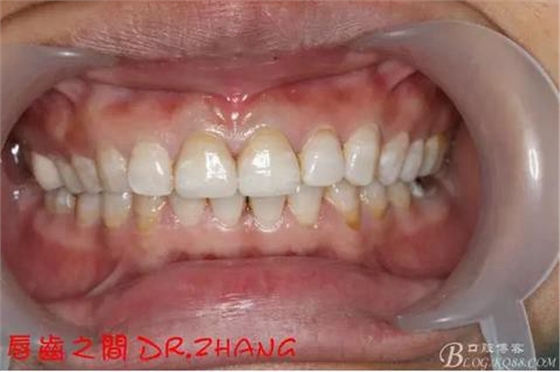

復(fù)診:臨時牙良好 患者自訴無不適癥狀 去除臨時修復(fù)體 排齦 清理牙面 試戴全瓷修復(fù)體后粘結(jié) 常規(guī)醫(yī)囑 不適隨診

總結(jié):沒有術(shù)前照片 預(yù)備牙體過長 顏色還是有差距